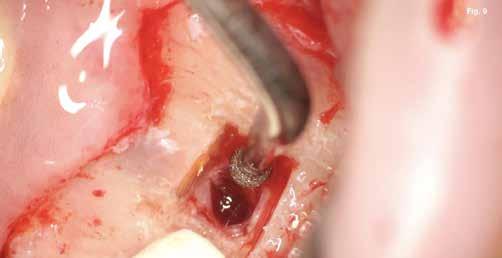

A szubmarginális teljes vastagságú lebenyt két felszabadító bemetszéssel végeztük egy 69-es számú, dupla lekerekített mikropengével (Swann–Morton) (6–7. ábra) A vestibularis csont ép volt, ezért csontablak-technikát alkalmaztunk és végeztünk (6–8. ábra) piezo készülékkel (Woodpecker DTE AI Surgery) és „US1, UC1” (Guilin Woodpecker Medical Instrument Co., LTD) hegyekkel. A blokkot az intraoperatív szakaszok alatt sóoldatban tartot-

tuk. Az apikális reszekciót (8. ábra) az „UC1” (Guilin Woodpecker Medical Instrument Co., LTD) segítségével végeztük el, és a gyökeret egy 3 mm-es „MM4” (Hu-Friedy Manufacturing Co. LLC) kerek tükörrel vizsgáltuk a VRF szempontjából (13. ábra). A gyökérvég polírozását (11. ábra) az „UL4” (Guilin Woodpecker Medical Instrument Co., LTD) segítségével végeztük. A csontos kripta küretizálása kézi küretezéssel történt, de a csontos kriptában lévő további hámbélés eltávolításával a gyógyulási folyamat felgyorsítása érdekében piezo „UL3” (Guilin Woodpecker Medical Instrument Co., LTD) piezo hegyet is használtunk (9–10. ábra). A három mm-es retropreparációt (14–17. ábra) a „JT2SA” hegy (B&L Biotech) segítségével végeztük el. A retropreparációt ismét ellenőriztük a guttapercha maradványok tekintetében, leöblítettük és papírhegyekkel meg-